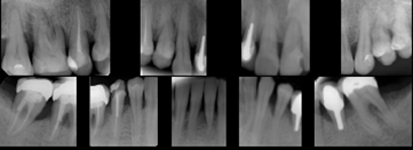

Periometr - první plně automatizovaný přístroj pro zjištění periodontálního statusu pacienta - diagnózy, léčby a profylaxe parodontitidy a dalších onemocnění. Díky správnému určení periodontálnímu statusu pacienta lze včas odhalit a minimalizovat objevující se obtíže.

Používá se i v implantologii, při stanovení diagnózy a léčby periimplantitidy (zánětu měkkých tkání a kosti v okolí implantátu).